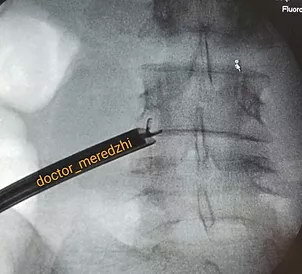

Для удаления фораминальных и экстрафораминальных грыж позвоночника наиболее оптимальным является использование эндоскопических трансфораминальных доступов. Под рентгенологическим и эндоскопическим контролем устанавливается рабочая канюля и эндоскоп в место непосредственного расположения грыжи в область межпозвонкового отверстия. Вид с камеры эндоскопа передается на экран монитора. Такой доступ позволяет подойти к грыже в обход опорных и нервных структур позвоночника, "коротким путем". Разрез на коже при таких операциях всего 7мм.

Схема удаления грыжи и рентген-контроль положения кончика инструмента в межпозвонковом отверстии во время операции.